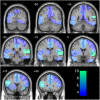

Bistability occurs when two alternative percepts can be derived from the same physical stimulus. To identify the neural correlates of specific subjective experiences we used a bistable auditory stimulus and determined whether the two perceptual states could be distinguished electrophysiologically. Fourteen participants underwent magnetoencephalography while reporting their perceptual experience while listening to a continuous bistable stream of auditory tones. Participants reported bistability with a similar overall proportion of the two alternative percepts (52% vs 48%). At the individual level, sensor space electrophysiological discrimination between the percepts was possible in 9/14 participants with canonical variate analysis (CVA) or linear support vector machine (SVM) analysis over space and time dimensions. Classification was possible in 14/14 subjects with non-linear SVM. Similar effects were noted in an unconstrained source space CVA analysis (classifying 10/14 participants), linear SVM (classifying 9/14 subjects) and non-linear SVM (classifiying 13/14 participants). Source space analysis restricted to a priori ROIs showed discrimination was possible in the right and left auditory cortex with each classification approach but in the right intraparietal sulcus this was only apparent with non-linear SVM and only in a minority of particpants. Magnetoencephalography can be used to objectively classify auditory experiences from individual subjects.